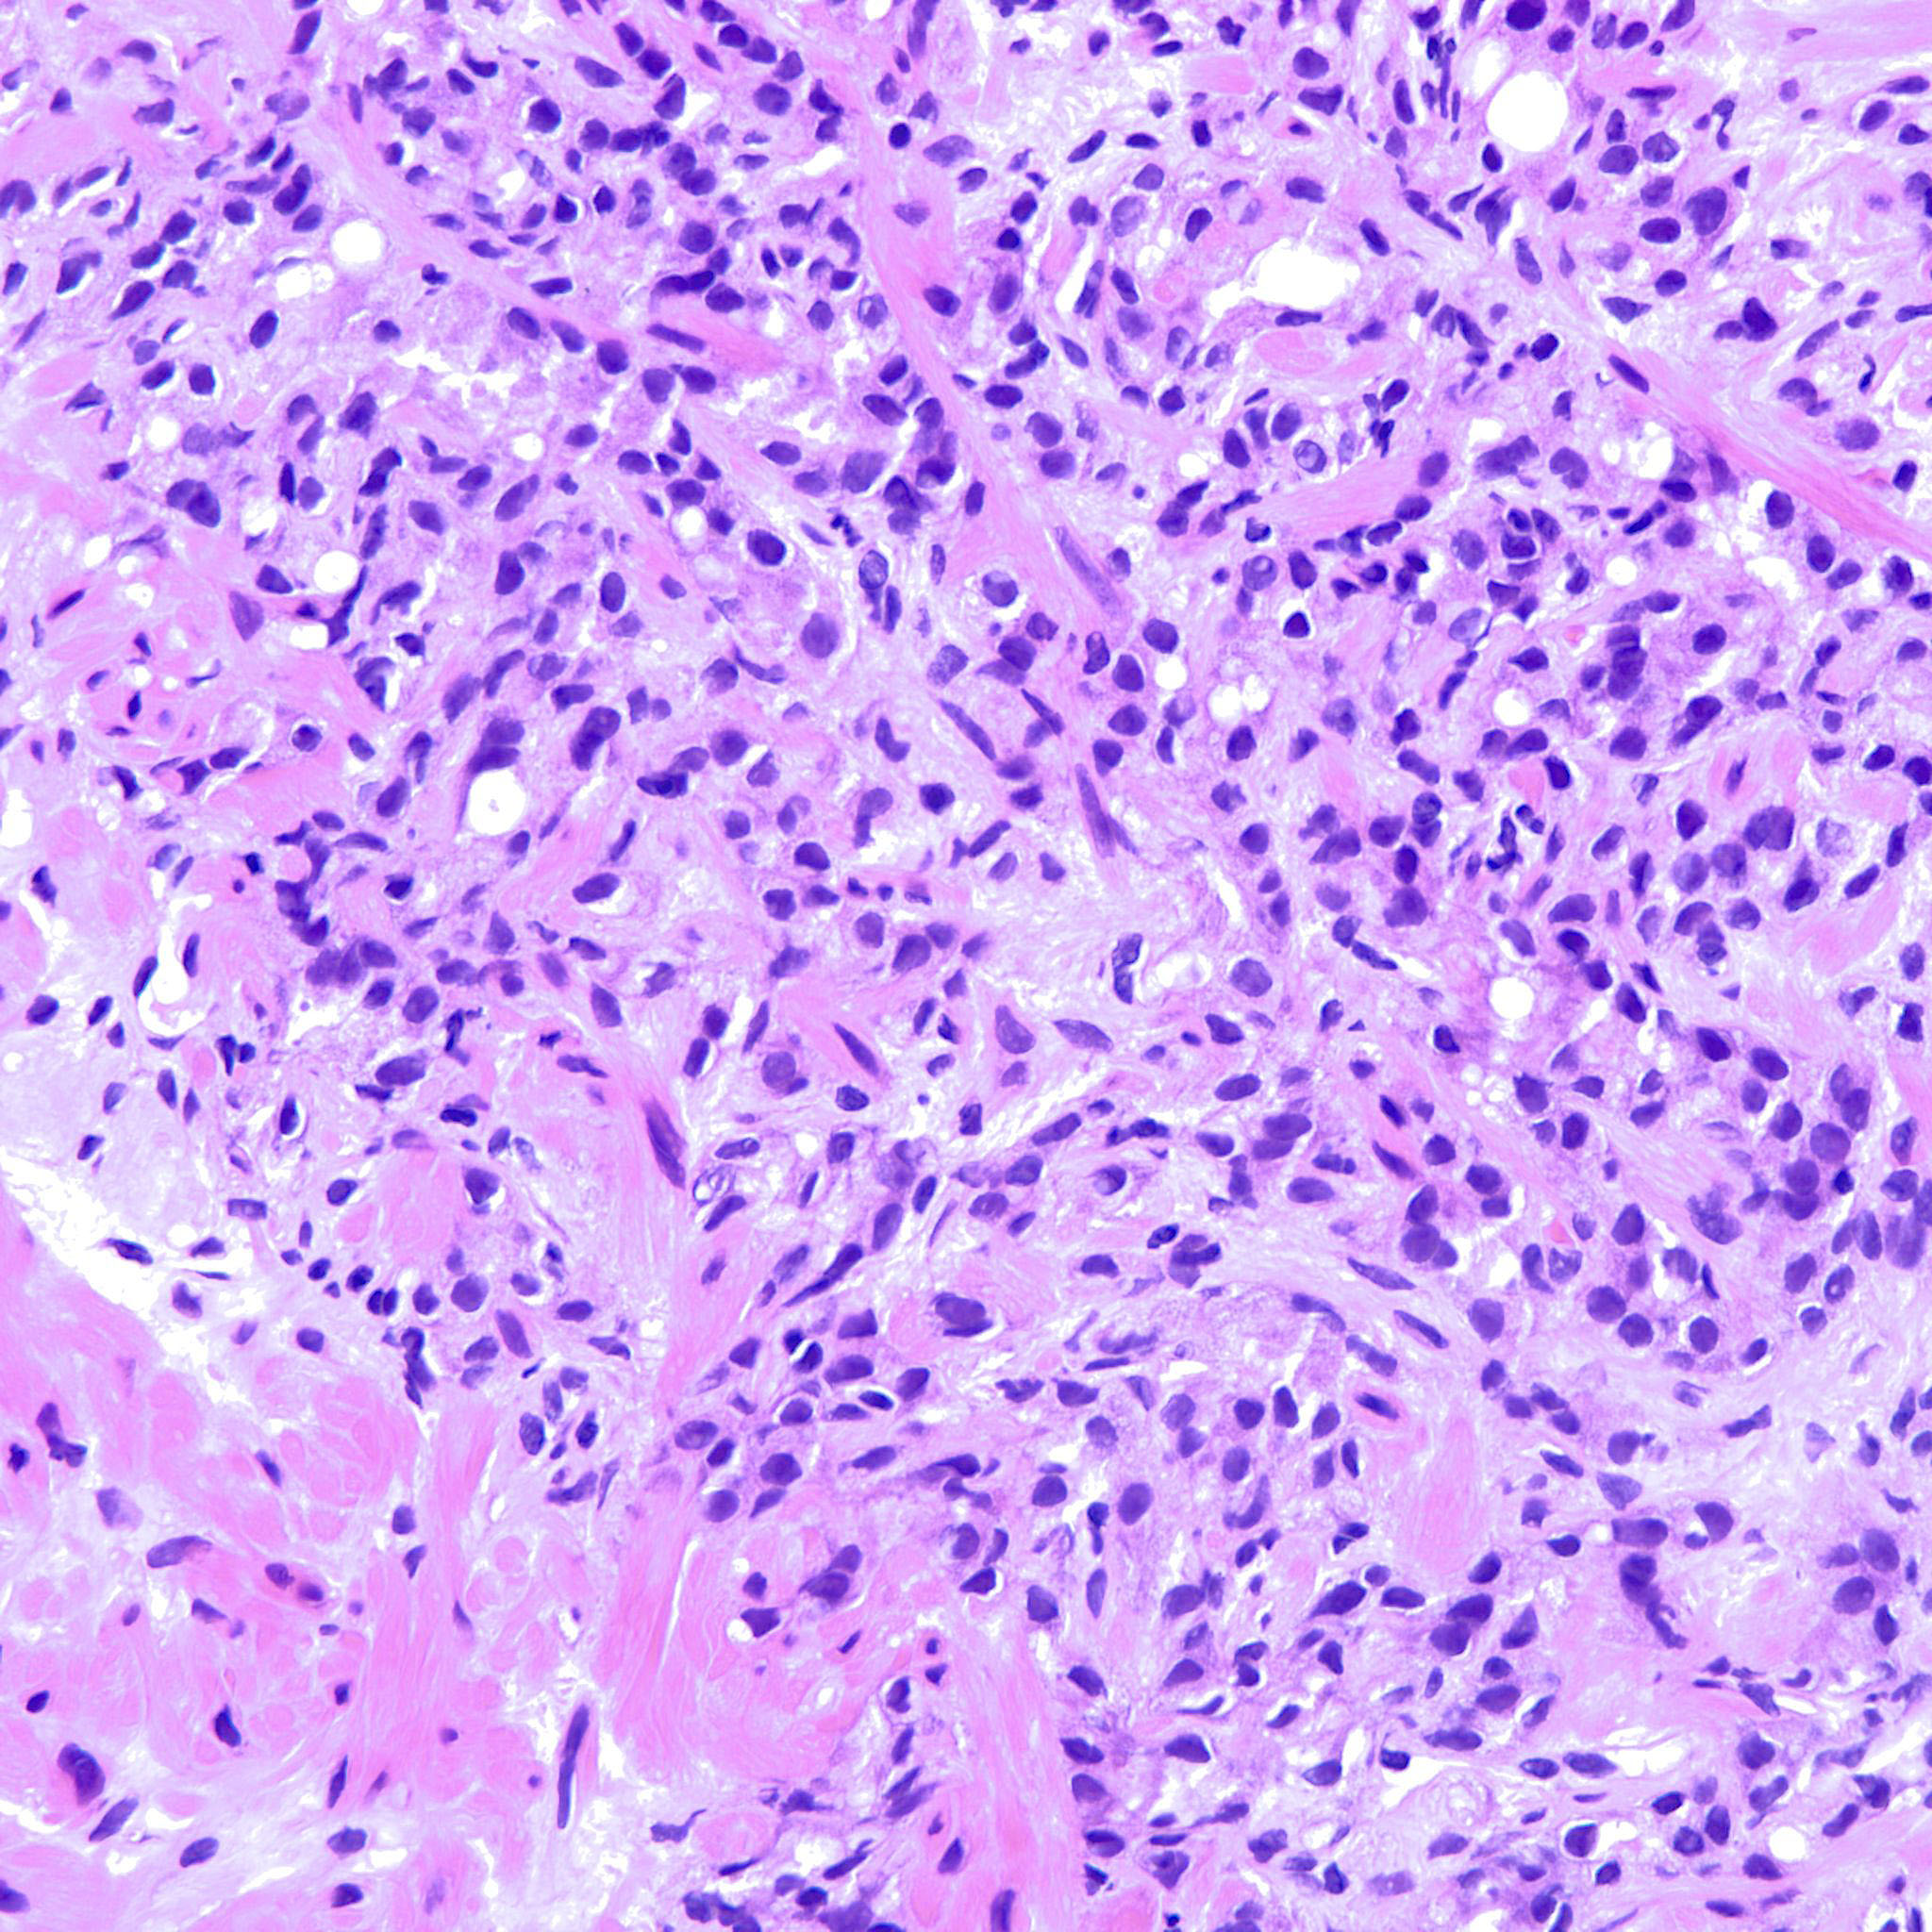

Prostate cancer grading

Case ID: 744